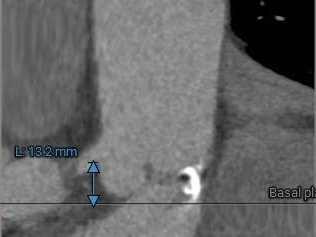

主动脉根部测量:

三叶式主动脉瓣,瓣叶增厚,R-N疑似钙化粘连,LVOT近似直筒型,非横位心。